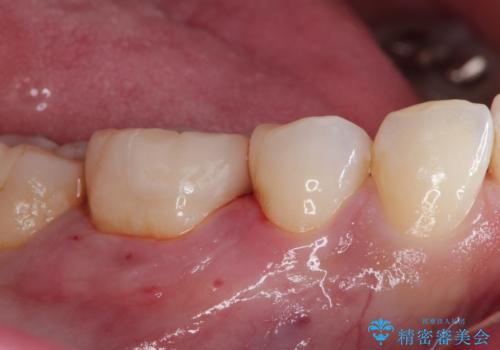

- メタルインレーによる審美障害を主訴に来院されました。

セラミックインレーに治療を行っております。

e-max プレスインレーにて修復治療を行っているため適合性及び審美性の高い治療を行うことができます。